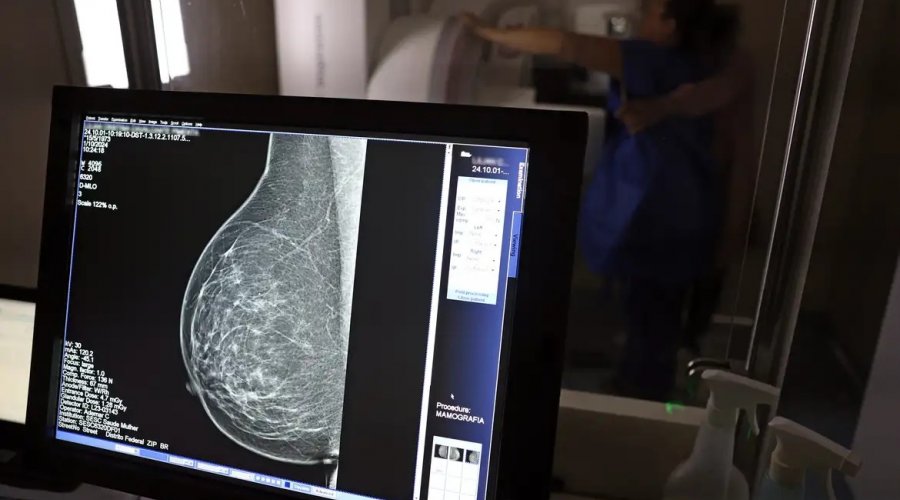

No Outubro Rosa, o Instituto Nacional de Câncer (Inca) estimou 73.610 novos casos este ano no país. É o câncer que mais mata mulheres no Brasil. As mulheres em tratamento pela doença têm o direito de receber o auxílio-doença ou o benefício de prestação continuada.

A vice-presidente da Comissão de Previdência Social Pública da Ordem dos Advogados do Brasil do Rio de Janeiro (OAB-RJ), Danielle Guimarães, destaca que o câncer de mama é uma das doenças que mais afetam mulheres no Brasil, impactando não apenas a saúde física e emocional, mas também a capacidade de trabalho e a segurança financeira das pacientes.